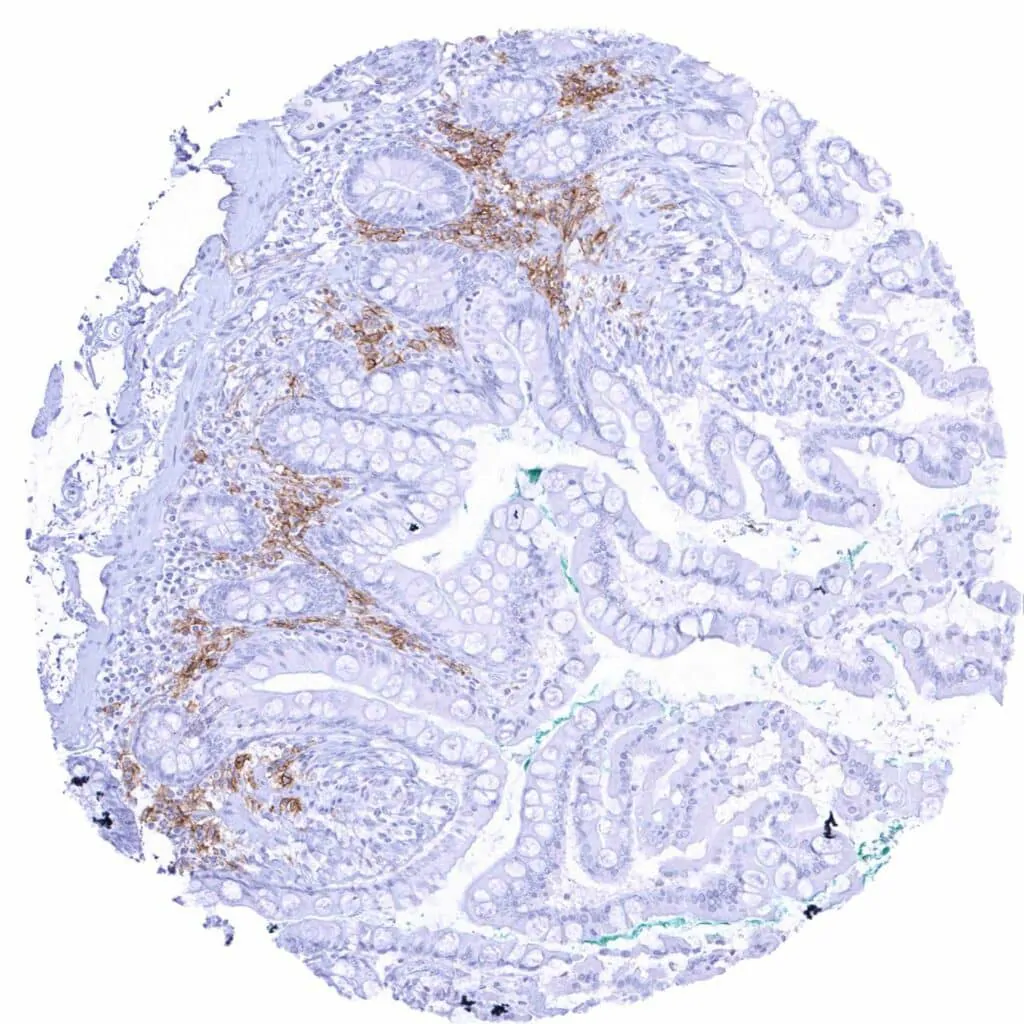

Duodenum, mucosa – Distinct CD38 staining of a subset of inflammatory cells